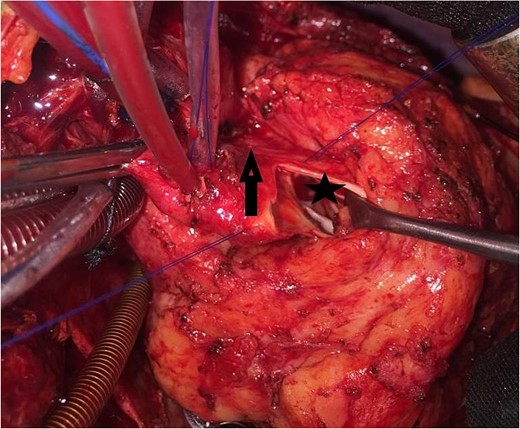

An 11-year-old girl was referred to our hospital with a main complaint of progressive exertional dyspnea. She had undergone surgical repair of SAS 6 years ago. Transthoracic echocardiogram (TTE) revealed the following findings: severe left ventricular hypertrophy, tunnel-like fibromembranous subaortic stenosis with a length of 10 mm, a peak gradient (PG) across the LVOT of 170 mmHg, and mild aortic regurgitation. Based on these findings, the patient was scheduled for elective surgical repair with a possible indication for MKO. The operation was performed via median sternotomy with great caution to avoid inadvertent rupture of any cardiac cavity due to heavy adhesions from the previous operation. The aorta was cannulated just below the takeoff of the innominate artery. Bicaval cannulation was performed to provide a bloodless field. Aortic cross-clamping was applied, and antegrade cold blood cardioplegic solution was administered via a catheter placed in the ascending aorta. The ascending aorta was opened transversely 1 cm above the sinotubular junction (Fig. 1). The aortic valve leaflets were examined carefully to confirm that the aortic valve could be preserved. LVOT was examined thoroughly, and it was clear that the stenosis in the subaortic area was so complex that simple resection through the aortic valve orifice would not be sufficient. The right ventricular outflow tract was opened transversely below the pulmonary valve. The conal papillary muscle was identified (Fig. 2). A right-angle instrument was introduced through the aortic orifice into the interventricular septum, and the tip of the instrument was used to perforate the conal septum to the left of the conal papillary muscle to prevent damage to the conduction system; the septal incision was completed with great caution to avoid damage to the aortic cusps and to extend the incision downward as necessary to completely relieve the stenotic subaortic area (Fig. 3). Interrupted 5/0 Prolene sutures were placed circumferentially around the septal incision to close the interventricular septal defect using a bovine pericardial patch to provide adequate widening of LVOT (Fig. 4). The right ventriculotomy was closed with a second bovine pericardial patch to avoid any possible obstruction of the right ventricular outflow tract (Fig. 5). The remainder of the operation was completed uneventfully. After 6 hours of mechanical ventilation, the patient was extubated, and she convalesced well postoperatively. TTE showed excellent results of the operation with PG across LVOT of 20 mmHg. On 1 year follow-up, the patient was asymptomatic and in very good general condition, and TTE findings confirmed the excellent result.

Intraoperative image showing the opened aorta. The arrow points to the aortotomy, and the star points to the stenotic left ventricular outflow tract through the aortic orifice.